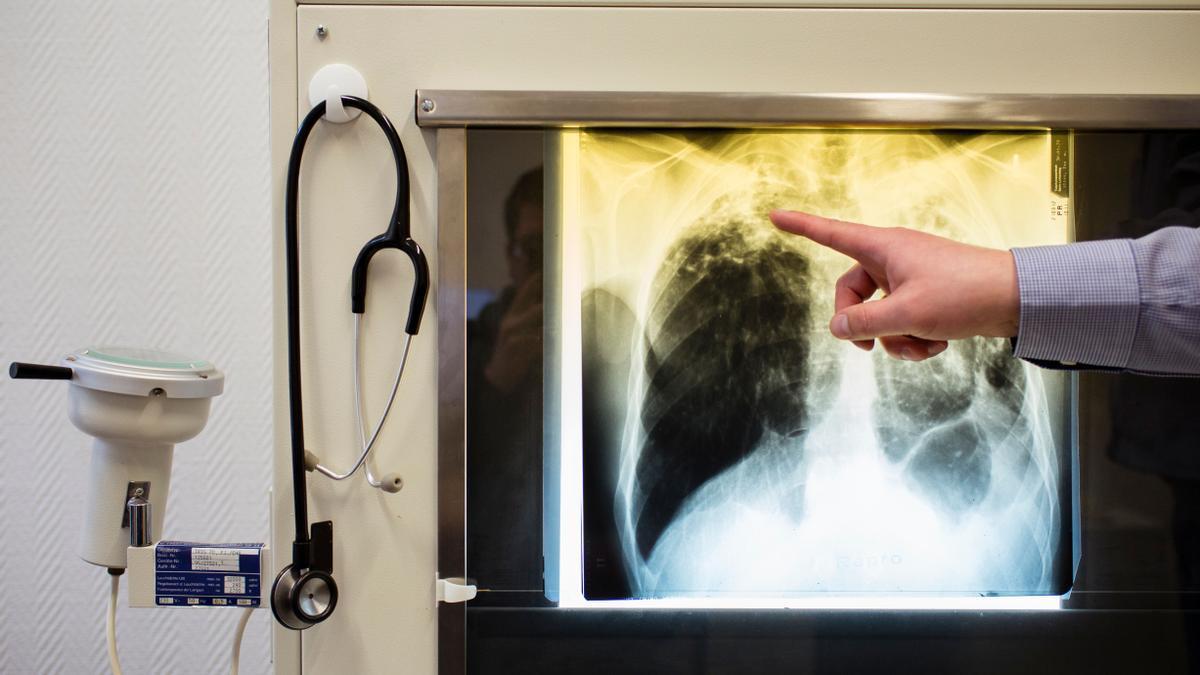

La Central Sindical Independiente y de Funcionarios (CSIF) ha interpuesto denuncia ante Inspección de Trabajo y ha acudido al Servicio de Salud y Prevención de Riesgos Laborales de la Gerencia Territorial de Justicia de Castilla-La Mancha, denunciando la situación del Servicio de Patología del Instituto de Medicina Legal y Ciencias Forenses de Toledo, cuyas instalaciones "no reúnen las condiciones mínimas de seguridad" y donde "se han producido cinco positivos por tuberculosis".

Estas deficiencias afectan de manera directa y con enorme gravedad a la plantilla: 5 de los 21 trabajadores del centro han estado expuestos al bacilo de la tuberculosis, "lo que evidencia un elevado riesgo biológico y la posible propagación de agentes infecciosos dentro de las instalaciones por sus condiciones totalmente insalubres".

Hasta el momento, "estos trabajadores no han desarrollado la enfermedad, pero se encuentran en situación de vigilancia y durante los próximos dos años tendrán que someterse a pruebas de manera periódica para comprobar que no sufren una tuberculosis activa".

Los trabajadores tuvieron constancia de este positivo por la prueba de Mantoux realizada a una técnico forense que estuvo trabajando de manera temporal en el Instituto de Medicina Legal y que se sometió a esta prueba en su nuevo puesto de trabajo en el Servicio de Salud de Castilla-La Mancha. CSIF exige que la prueba de Mantoux sea de obligada aplicación en el protocolo de Prevención de Riesgos Laborales de todo el personal forense.